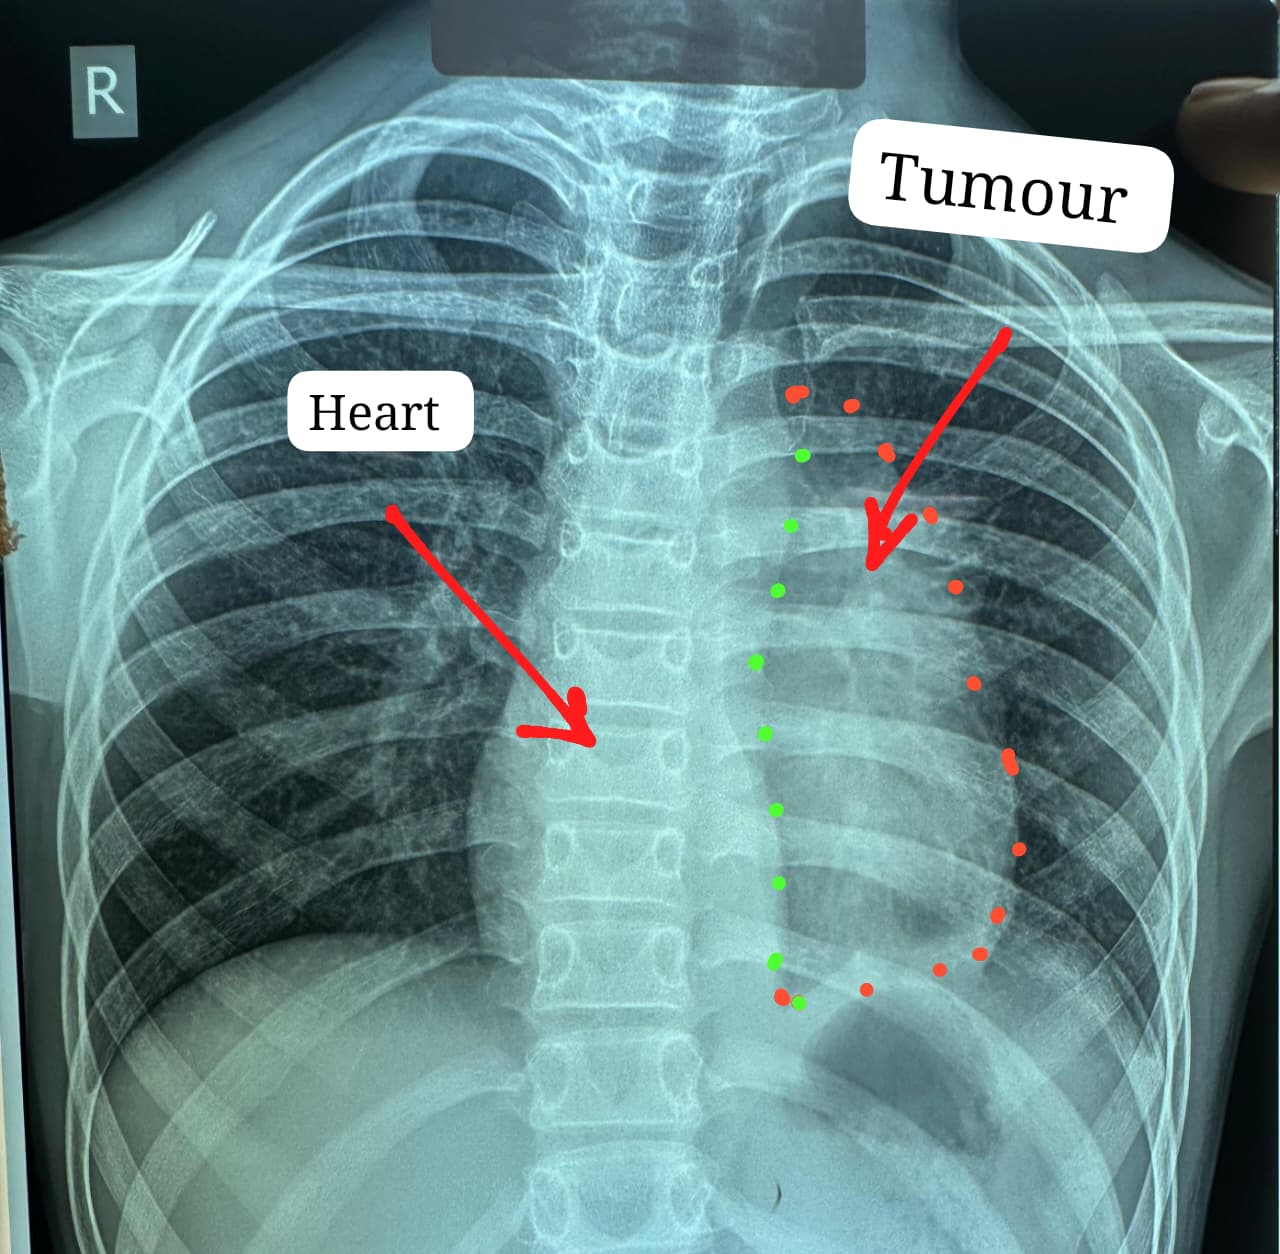

डॉक्टरों के अनुसार यह ट्यूमर सामान्यतः 40 से 60 वर्ष के लोगों में पाया जाता है और बच्चों में इसका मिलना अत्यंत दुर्लभ है। यह ट्यूमर हृदय, पेरिकार्डियम, फ्रेनिक नर्व महाधमनी (एओर्टा), मुख्य पल्मोनरी आर्टरी, लेफ्ट एट्रियम और फेफड़े से चिपका हुआ था। ऐसे मामलों में ट्यूमर को पूरी तरह निकाल पाना (आर-0 रिसेक्शन) लगभग असंभव माना जाता है, लेकिन अस्पताल में उपलब्ध हार्ट-लंग मशीन की मदद से यह संभव हो पाया।

मुख्य ट्यूमर के अलावा फेफड़े की प्लूरल कैविटी में फैले तीन अन्य सैटेलाइट ट्यूमर को भी सावधानीपूर्वक निकाला गया, ताकि भविष्य में कैंसर दोबारा फैलने की संभावना न रहे। निकाले गए ट्यूमर का आकार लगभग 12×8 सेंटीमीटर और वजन करीब 400 ग्राम था।

ऑपरेशन के दौरान किसी भी आपात स्थिति के लिए हार्ट-लंग मशीन तैयार रखी गई थी। लगभग चार घंटे चली सर्जरी के दौरान हार्ट की झिल्ली, फ्रेनिक नर्व तथा फेफड़े के कुछ हिस्से को भी निकालना पड़ा। साथ ही हार्ट के लेफ्ट एट्रियम को भी रिपेयर किया गया क्योंकि ट्यूमर लेफ्ट एट्रियम से चिपका हुआ था। इस दौरान मरीज को चार यूनिट रक्त की आवश्यकता पड़ी।